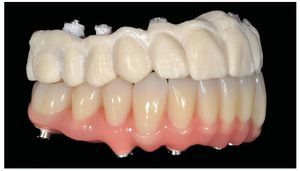

Pese a ello, es importante someter las estructuras a un control visual y mecánico, a fin de corregir eventuales discrepancias menores (figs. 99 a 102). A continuación se procede al montaje utilizando dientes protésicos prefabricados de composite (SR Phonares NHC, Ivoclar Vivadent, Ellwangen, Alemania), los cuales reproducen el tipo funcional correspondiente en virtud de sus propiedades morfológicas y estructurales y se integran armoniosamente en cuanto a su longitud dental (figs. 103 a 105). Durante la comprobación de las restauraciones protésicas, se evalúan clínica y radiológicamente ante todo la pasividad y la precisión del ajuste de la estructura. Acto seguido se lleva a cabo una comprobación de la oclusión y de la dimensión vertical, del estado de las prótesis y del tejido blando en la cresta alveolar, así como la verificación del espacio libre lingual, incluida la fonación, y el apoyo de los labios y las mejillas (figs. 106 y 107). También se debe comprobar la facilidad de higiene de la restauración de acuerdo con las habilidades manuales del paciente. A continuación se debe verificar la posición tridimensional de los dientes anteriores con los labios cerrados y durante la sonrisa, así como el aspecto global de la rehabilitación protésica.

Figs. 103 a 105. Recubrimiento estético de las estructuras con dientes protésicos prefabricados de composite. Vista frontal y lateral a derecha e izquierda.

Durante la fase de laboratorio final pueden ser necesarios diversos ajustes estéticos y funcionales. A continuación puede confeccionarse la restauración definitiva (figs. 108 a 111). Posteriormente se procede al control final mediante sendos montajes cruzados de la restauración definitiva y del modelo de planificación (figs. 112 a 115).

Figs. 108 a 111. Vista frontal y lateral de los puentes implantosoportados terminados.